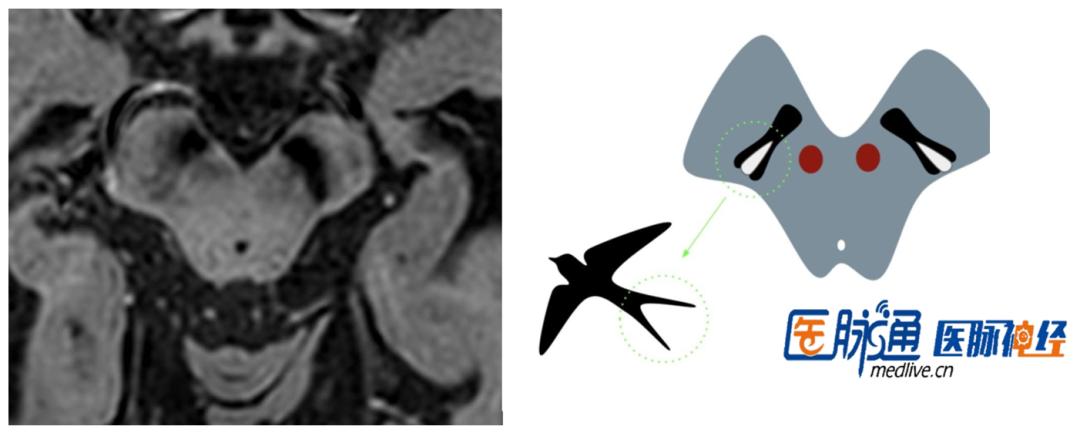

看图识病。

答案:左侧燕尾征消失。补充病例:男性,75岁患者运动迟缓,静止性震颤,肢体强直,右侧为重,诊断帕金森病。燕尾征消失多见于帕金森病、帕金森叠加综合征、路易体痴呆等变性病中。